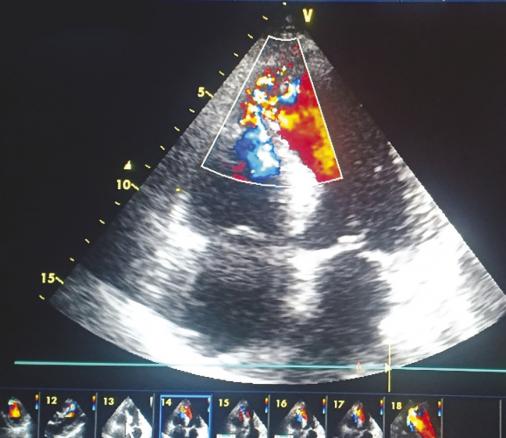

Cet homme de 70 ans à très haut risque cardiovasculaire cumulant diabète, hypertension artérielle et tabagisme, consultait 48 heures après une douleur thoracique angineuse, pour une dyspnée de repos. À l’examen on notait des signes de décompensation cardiaque droite, avec à l’auscultation un souffle holosystolique râpeux en parasternal gauche, irradiant en rayon de roue. L’électrocardiogramme montrait des séquelles d’ischémie en antérieur étendu et l’échocardiographie visualisait une large communication interventriculaire (CIV) musculaire avec shunt gauche-droite (fig. 1 et 2 ). La coronarographie montrait des lésions bitronculaires. La revascularisation chirurgicale et la fermeture de la CIV étaient réalisées sous circulation extracorporelle avec des suites opératoires simples.

La communication interventriculaire compliquant un infarctus du myocarde est une complication rare mais redoutable, associée à un taux de mortalité très élevé qui avoisine 97 % à 30 jours de l’infarctus.1 Son diagnostic repose sur la suspicion clinique et la confirmation échocardiographique.